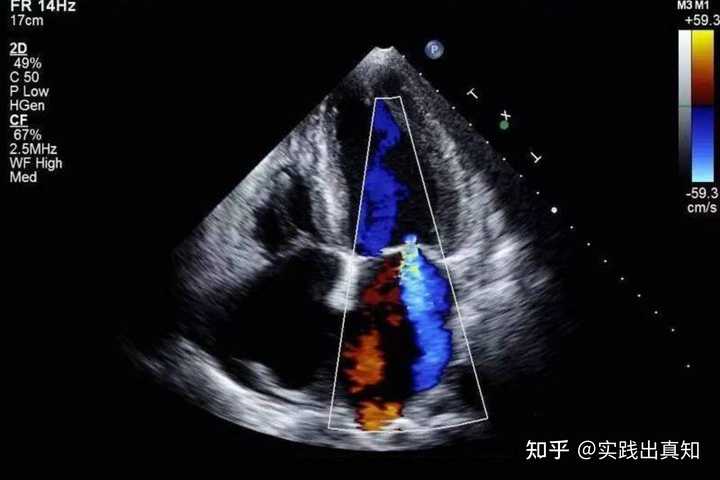

心脏彩超无法清晰地显示冠状动脉的内部情况。冠状动脉的直径只有几毫米,而彩超的分辨率有限,无法判断里面是否有动脉粥样硬化斑块、狭窄或者血栓。诊断冠状动脉需要做冠状动脉CTA(冠脉造影)。